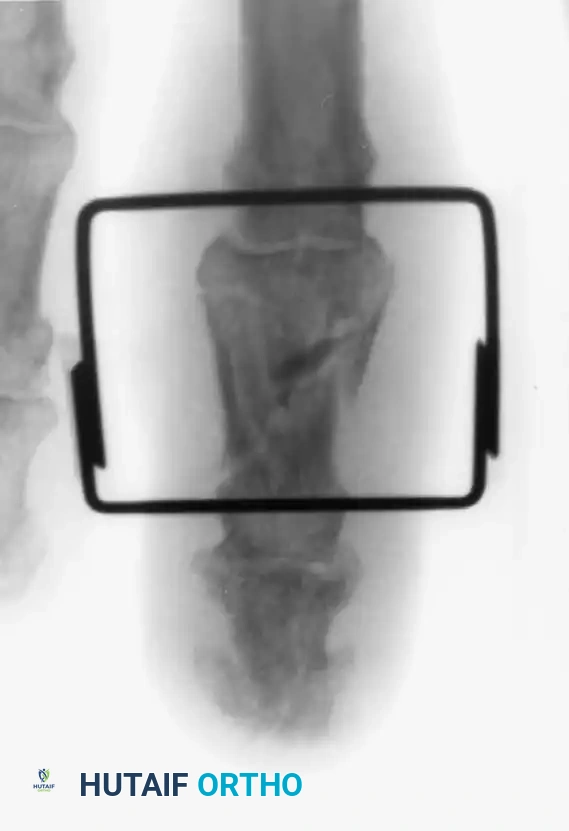

4. Chronic Instability: Autogenous Hemihamate Osteoarticular Grafting

When PIP joint dorsal subluxation persists even with 30 degrees of PIP joint flexion, or when >50% of the volar lip is destroyed and cannot be fixed, an autogenous hemihamate osteoarticular graft is recommended (Williams et al.).

A size-matched segment of the distal hamate articular surface (between the 4th and 5th metacarpal facets) is harvested. This graft perfectly matches the bicondylar contour of the middle phalanx base.

Surgical Pearl: Despite the dramatic stability achieved intraoperatively with a hemihamate graft, it is highly recommended to protect the repair with provisional transarticular K-wire pinning for 2 weeks to prevent graft displacement during early healing.